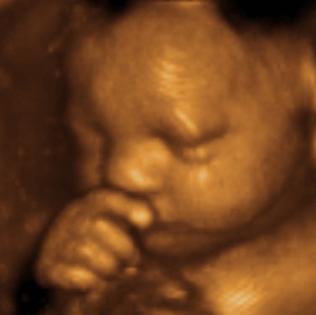

4 Baby 20 Weeks 3d Ultrasound 3d Ultrasound Vancouver Bc